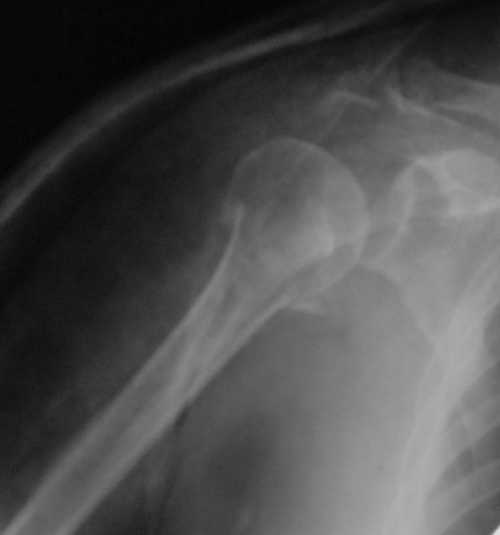

Снимки на 1-е сутки после репозиции и на 8- сутки после репозиции.